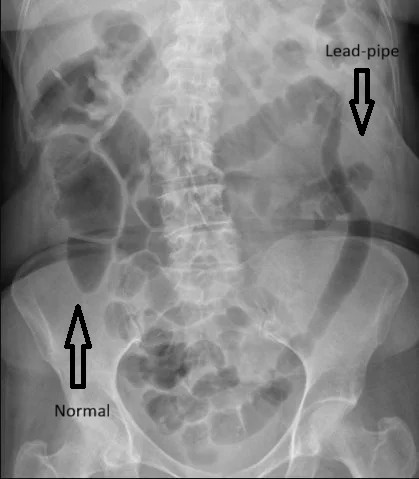

- Barium enema (less common now): Shows loss of haustra, resulting in a “lead pipe” appearance.

- Loss of haustra